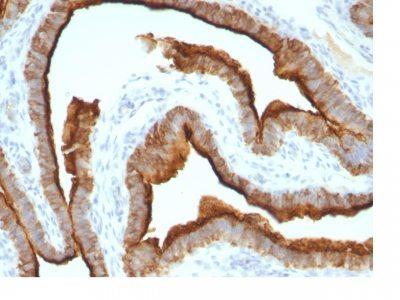

This MAb recognizes full-length MUC1 in a glycosylation-independent manner and can bind to the fully glycosylated protein. The dominant epitope of this MAb is APDTR in the VNTR region. It reacts with the core peptide of the MUC1 protein, which is a member of a family of mucin glycoproteins that are characterized by high carbohydrate content, O-linked oligosaccharides, high molecular weight (>200 kDa) and an amino acid composition rich in serine, threonine, proline and glycine. The core protein contains a domain of 20 amino-acid tandem repeats that functions as multiple epitopes for the MAb. Incomplete glycosylation of some tumor-associated mucins may lead to variable unmasking of the multiple peptide epitopes leading to the observed differences in staining intensity between normal and malignant tissues. This MAb reacts with both normal and malignant epithelia of various tissues including breast and colon.Primary antibodies are available purified, or with a selection of fluorescent CF® Dyes and other labels. CF® Dyes offer exceptional brightness and photostability. Note: Conjugates of blue fluorescent dyes like CF®405S and CF®405M are not recommended for detecting low abundance targets, because blue dyes have lower fluorescence and can give higher non-specific background than other dye colors.

MCF-7 or MDA-231 cells. Breast, colon, ovarian, endometrial carcinoma.

Immunohistology formalin-paraffin 0.25-0.5 ug/mL|Staining of formalin-fixed tissues requires boiling tissue sections in 10 mM citrate buffer, pH 6.0, for 10-20 min followed by cooling at RT for 20 minutes|Flow Cytometry 0.5-1 ug/million cells/0.1 mL|Immunofluorescence 1-2 ug/mL|Optimal dilution for a specific application should be determined by user